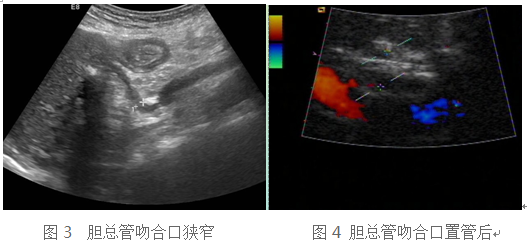

54岁的曾先生因肝硬化肝衰竭在外院行肝移植手术,术后三个月直接胆红素(DBIL)逐步升高。入住我院移植科后,常规肝移植术后超声检查发现胆总管吻合口呈鸟嘴样狭窄,肝门部胆总管呈节段性扩张,符合胆总管吻合口狭窄(图3)。经过介入科ERCP胆总管扩张术(图4),患者胆红素下降至正常水平后出院。